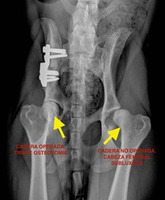

En las caderas displásicas a edades muy tempranas se comienza a notar una “hiperlaxitud coxofemoral”, ( es decir, las caderas están poco firmes dentro de la cápsula articular: la membrana que envuelve la articulación y que debería estar más tensa). Como consecuencia de esto, los dos componentes de la articulación: cabeza femoral y acetábulo de la pelvis, no encajan perfectamente uno con otro, y cada vez se alejan más, con lo que la congruencia articular cada vez se ve más comprometida ( ver foto). El resultado final de la displasia cuando ha transcurrido el suficiente tiempo es la artrosis de cadera o coxartrosis ( ver artrosis en el menú).

- ·CADERA NORMAL

Las cabezas femorales son esféricas, el ángulo que forman con el cuello del fémur es de 145 grados y están bien encajadas dentro del acetábulo de la pelvis, siendo concéntricas con éste